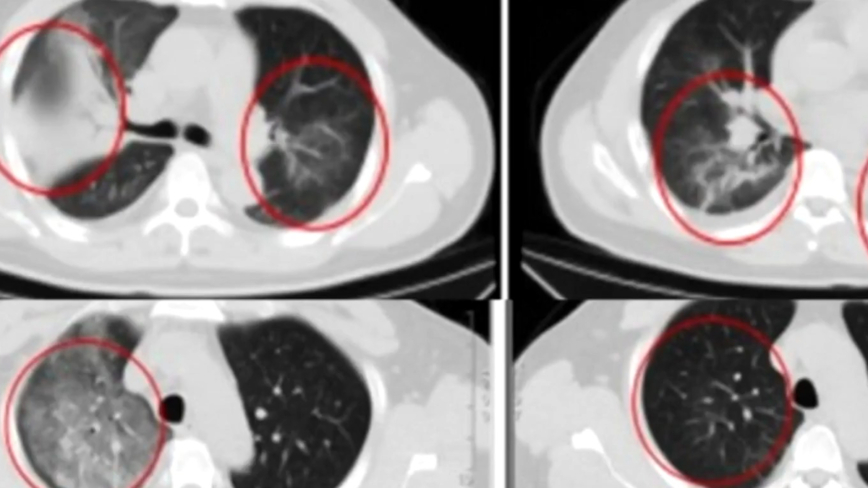

【新!唐!人:北京时间2025年01月09日讯】江苏省一名顾姓男子,近日从非洲返回后,出现发烧、咳嗽、乏力以及肌肉酸痛等症状,患者就诊时。

双肺已经出现大面积病变,就医后确诊是罕见的人畜共通传染病“Q热”,消息登上热搜,引起多方关注。